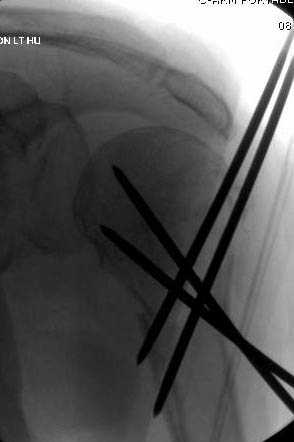

Наш недавний случай перкутанной фиксации "методом

Сиэтла" спицами 2.8 мм с резьбой на конце.

Наличие рентген контроля (ЭОП) помогает во время

репозиции и фиксации, но многие коллеги умудряются без рентгена фиксировать несколькими спицами перкутанно.

Из-за тенденции миграции осторожно со спицами,

особенно у пожилых, слабые кости не выдерживают

нагрузку, были случаи миграции, обнаруженные при первом же амбулаторном приеме, поэтому методика Лазарева напряженными спицами более приемлема, особенно у тех, кто испытывает нехватку фиксирующих конструкций (на сайте

имеется описание техники).